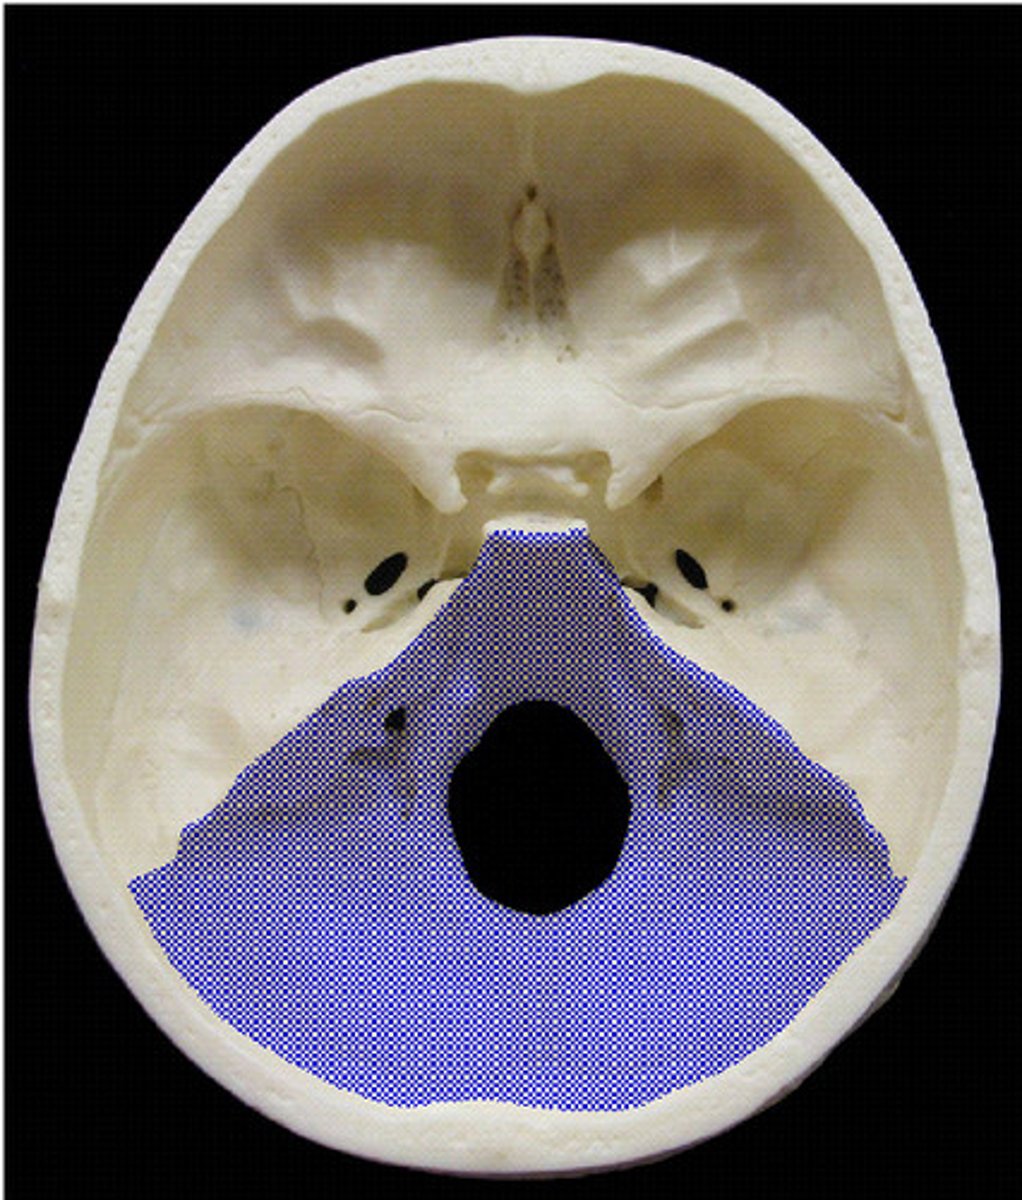

posterior cranial fossa